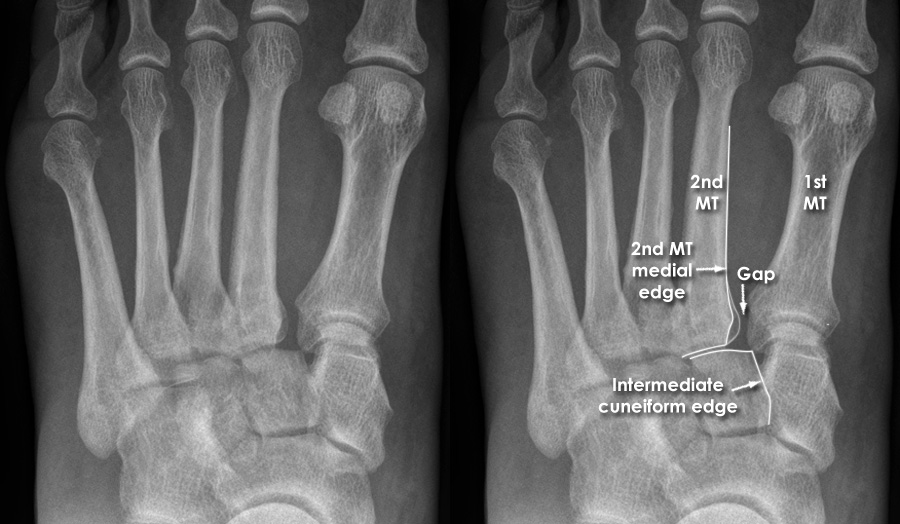

Midfoot Fracturedislocations UW Emergency Radiology Foot Joint Trauma Learn about the many causes of foot joint pain, from injury to arthritis, and discover tips for managing symptoms. Patients typically present with varying signs and. Lisfranc (midfoot) injuries result if bones in the midfoot are broken or ligaments that support the midfoot are torn. Lisfranc injuries are almost always caused by a fall, slip or trauma to the foot.. Foot Joint Trauma.

Trauma Xray Lower limb gallery 2 Foot Lisfranc injury Foot Joint Trauma An injury to the tarsometatarsal joint is known by the eponym “lisfranc injury.” these types of injuries include sprains of the midfoot ligaments,. They most often involve the metatarsals and toes. Learn about the many causes of foot joint pain, from injury to arthritis, and discover tips for managing symptoms. The severity of the injury can vary from simple to. Foot Joint Trauma.